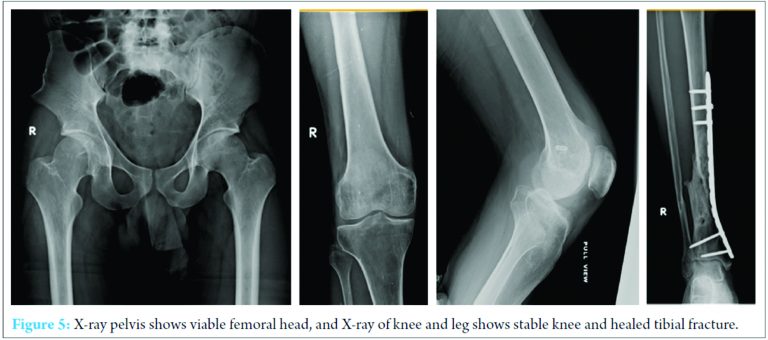

At 6 weeks, external fixator was removed and bone grafting was done for the distal tibial fracture and the right knee gently manipulated. The distal tibial fracture healed in 4 months with good recovery of common peroneal nerve. The knee flexion was 0-130° with posterior sagging and multidirectional instability. Magnetic resonance imaging (MRI) of right knee showed posterior cruciate ligament (PCL) avulsion fracture and lateral collateral ligament avulsion fracture (Fig. 4). It was planned arthroscopic evaluation which showed a torn PCL at tibial attachment and torn anterior cruciate ligament (ACL) at anterolateral bundle but the continuity maintained with posterolateral bundle. Arthroscopic PCL reconstruction using bio screws and open posterolateral corner repair using hamstring graft and endobutton was done. Post-operative rehabilitation included the protocol for multi-ligament instability. At 2 years follow-up, he had full range of movements at the right hip and knee. Radiographs of the pelvis showed a viable femoral head without signs of avascular necrosis. There was complete recovery of the common peroneal nerve (Fig. 5, 6). The knee was stable and he returned to his preinjury level of activity.